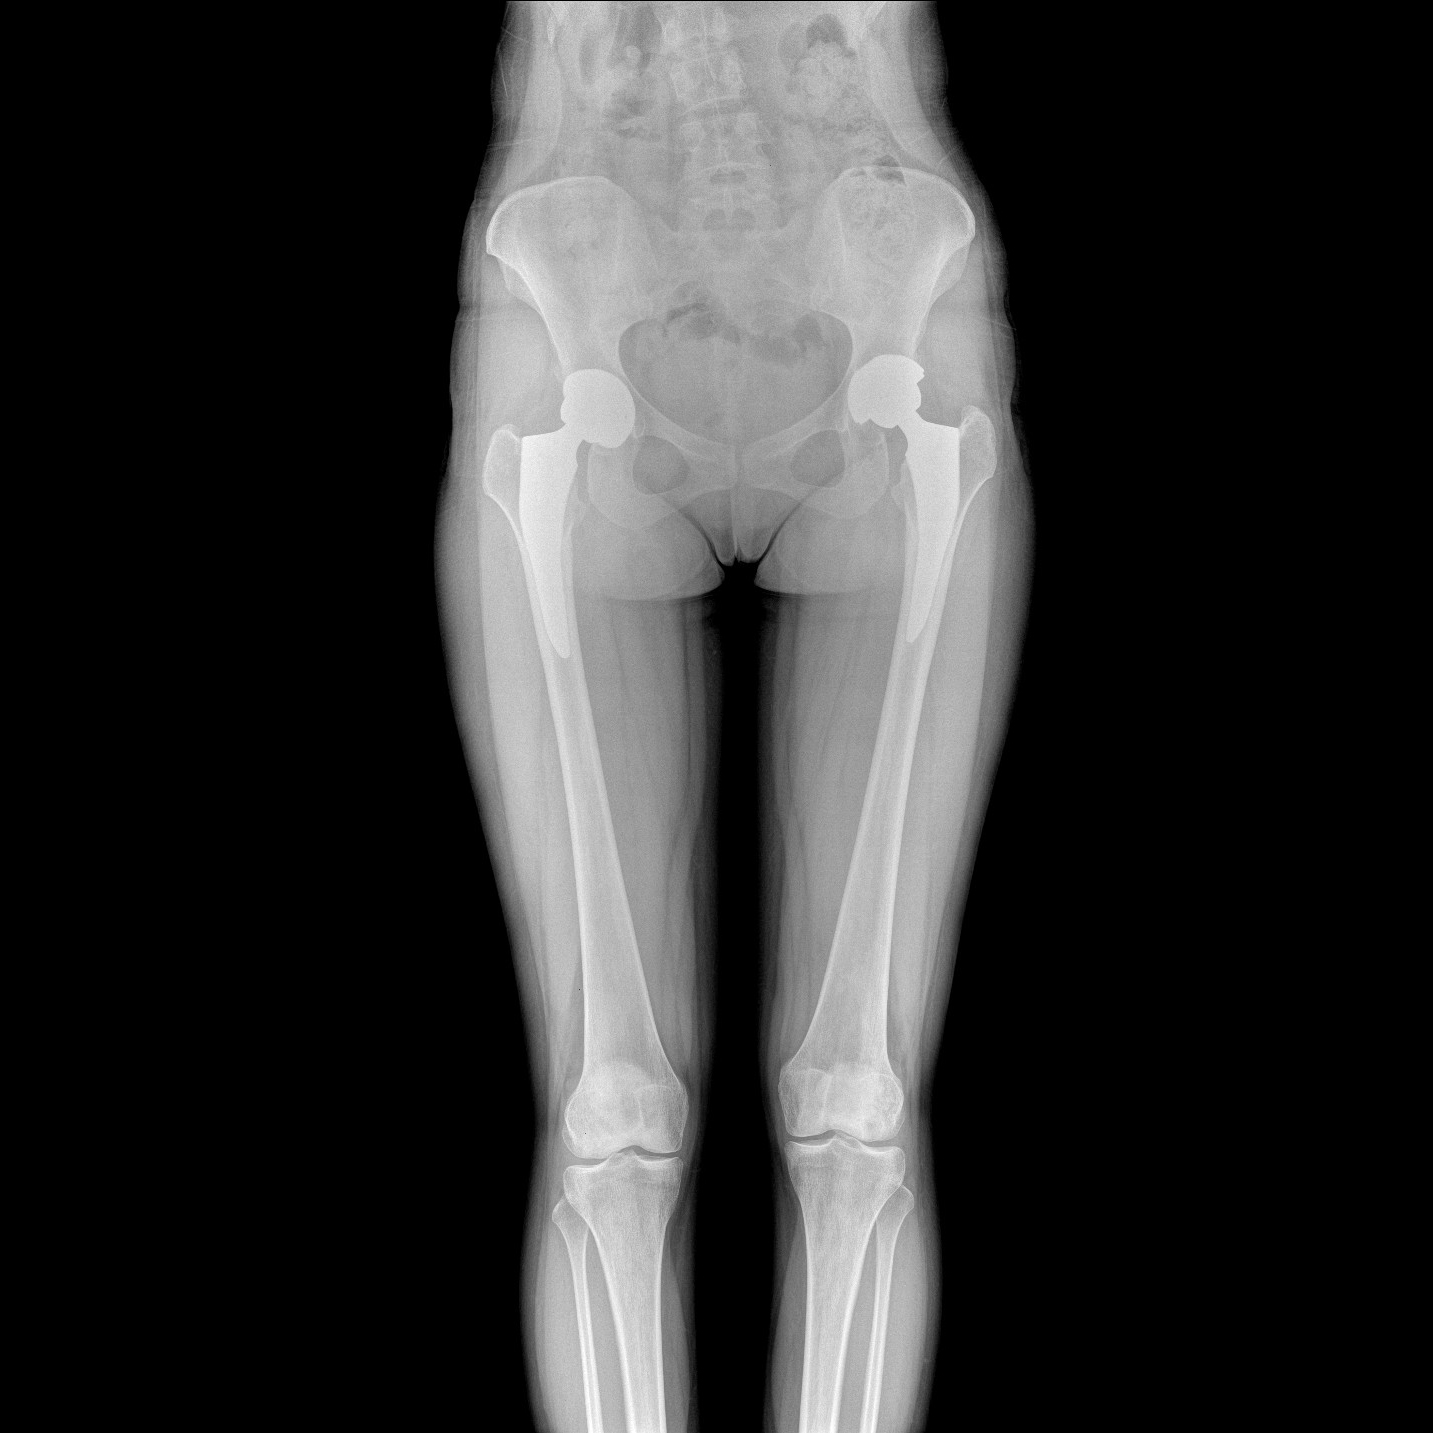

17"*34"有效視野,一次成像不拼接。相較于多張攝影再軟件拼接的DR設(shè)備,PLX8600解決了拼接圖像存在密度不均勻,拼接處圖像配準(zhǔn)和放大效應(yīng)等問題,給臨床帶來了大視野影像解決方案,可一次性覆蓋全脊柱或雙下肢影像。